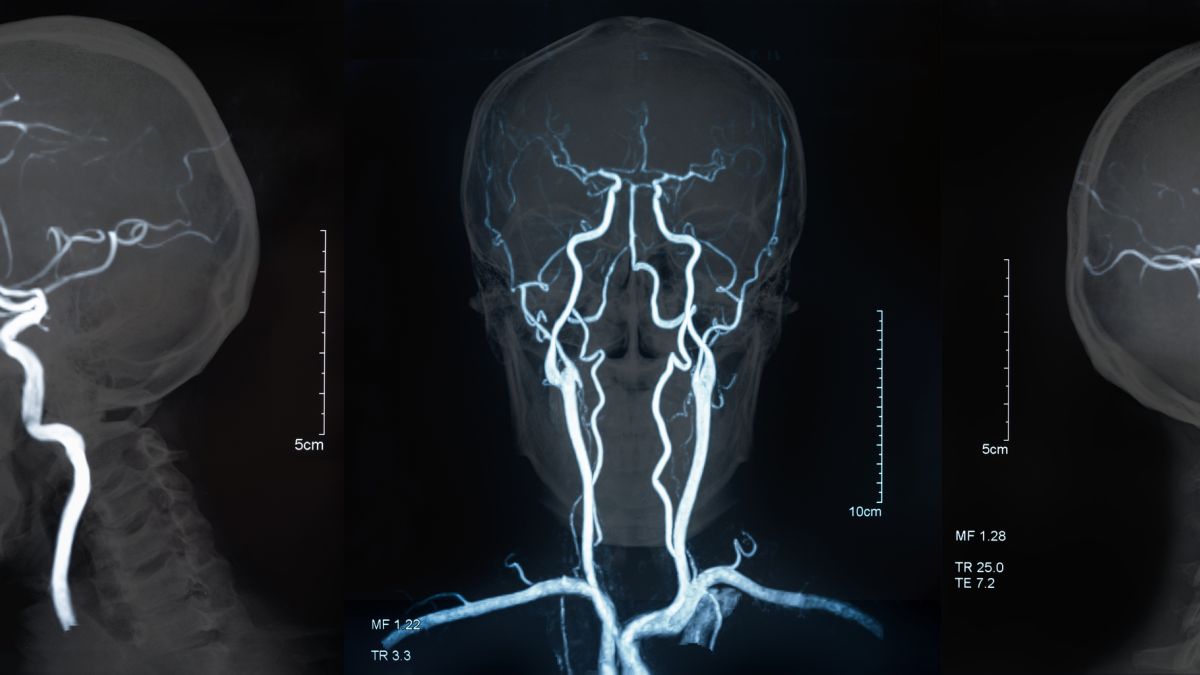

Ochsner Health has nationally recognized neurocritical care programs in Lafayette and New Orleans, Louisiana, where we create and implement individualized care plans for hundreds of patients a year with strokes, severe brain illnesses and brain injuries.

• Stroke

• Subarachnoid hemorrhage (bleeding in the space that surrounds the brain)

• Intracerebral hemorrhage (bleeding into the brain tissue)